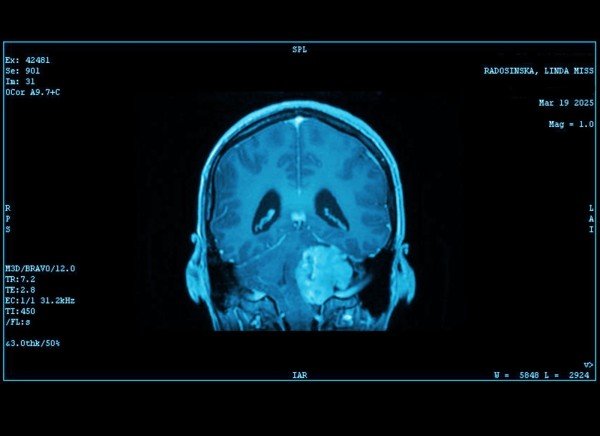

Australia, 28th Oct 2025 – In March 2025, Melbourne artist Linda Radosinska faced an unimaginable challenge. Diagnosed with a large acoustic neuroma, a type of brain tumor, she underwent a grueling 13-hour surgery to remove it. But instead of letting her journey be defined by hardship, Linda chose to transform it into something meaningful: Neurospicy Art.